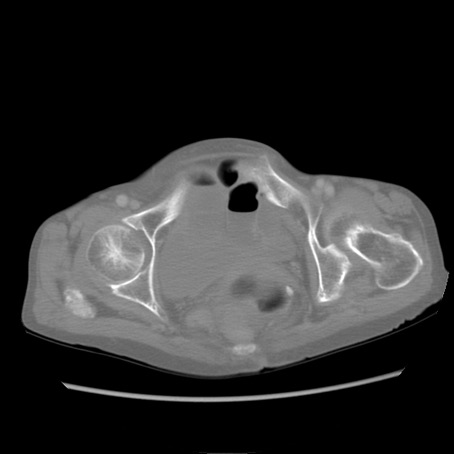

症例25(横断像)

【症例】80歳代女性

【主訴】胸のつかえ感

【現病歴】約9時間前に食後から胸のつかえた感じあり、嘔吐あり、来院。

【既往歴】胃癌(全摘)、胆摘、虫垂炎

【身体所見】心窩部に圧痛あり、反跳痛なし。

【データ】WBC 5700、CRP 0.05